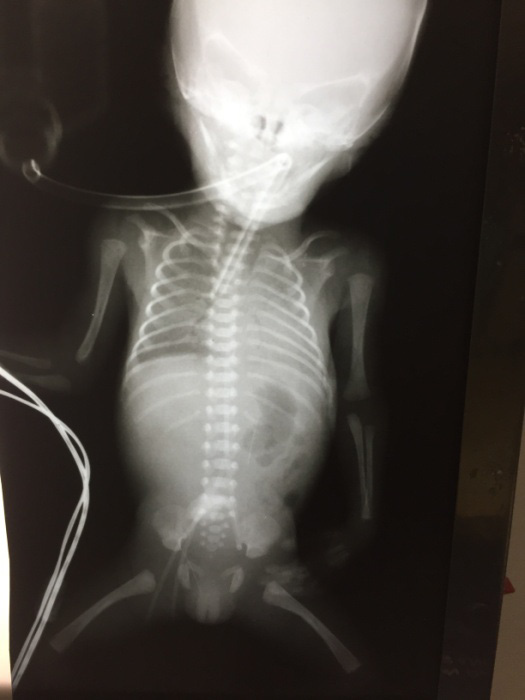

A figura a seguir apresenta o raio X de tórax do paciente.

Administrada primeira dose de surfactante com aproximadamente 1h30min de vida. Ao exame apresenta-se estável, tolerando reduzir parâmetros, mas apresentando ausculta respiratória reduzida à esquerda.

De acordo com as Diretrizes 2016 da Sociedade Brasileira de Pediatria, o valor ideal e adequado da profundidade de inserção da cânula traqueal conforme a idade gestacional referida no caso clínico é: